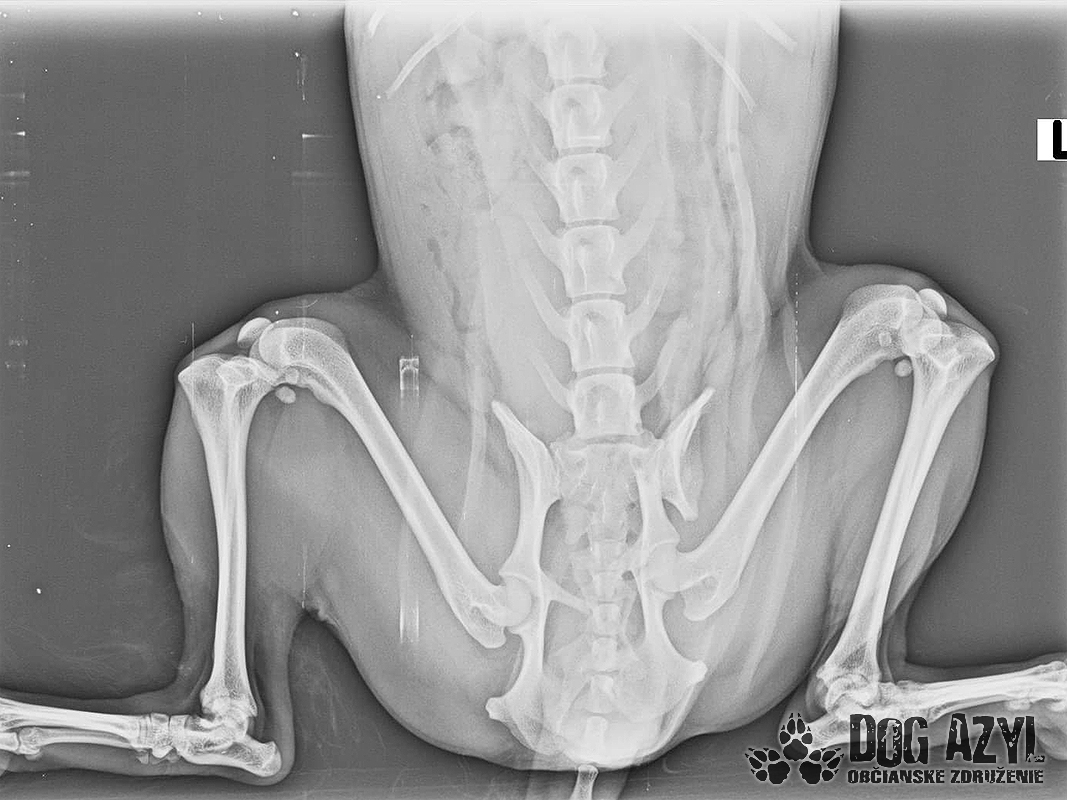

Bola neskutočne zanedbaná, hladná a dolámaná. Panvu má zlomenú na troch miestach, od úderu jej praskol močový mechúr a mala na sebe snáď všetky blchy sveta, žrali ju zaživa. Zotavuje sa.. Pomaličky, ale zotavuje sa po náročných operáciách a dúfame, že bude opäť v poriadku. Bude potrebovať rehabilitovať, aby vedela opäť behať, ale zabezpečíme jej úplne všetko, čo bude treba!!